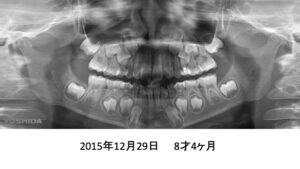

もう1症例、8才4ヶ月の患者さんです。

パノラマでは、永久歯が入るスペースが足りないように見えます。

4年後です。治療は何もしていません。

さらに2年後、全ての歯がちゃんと萌出しました。